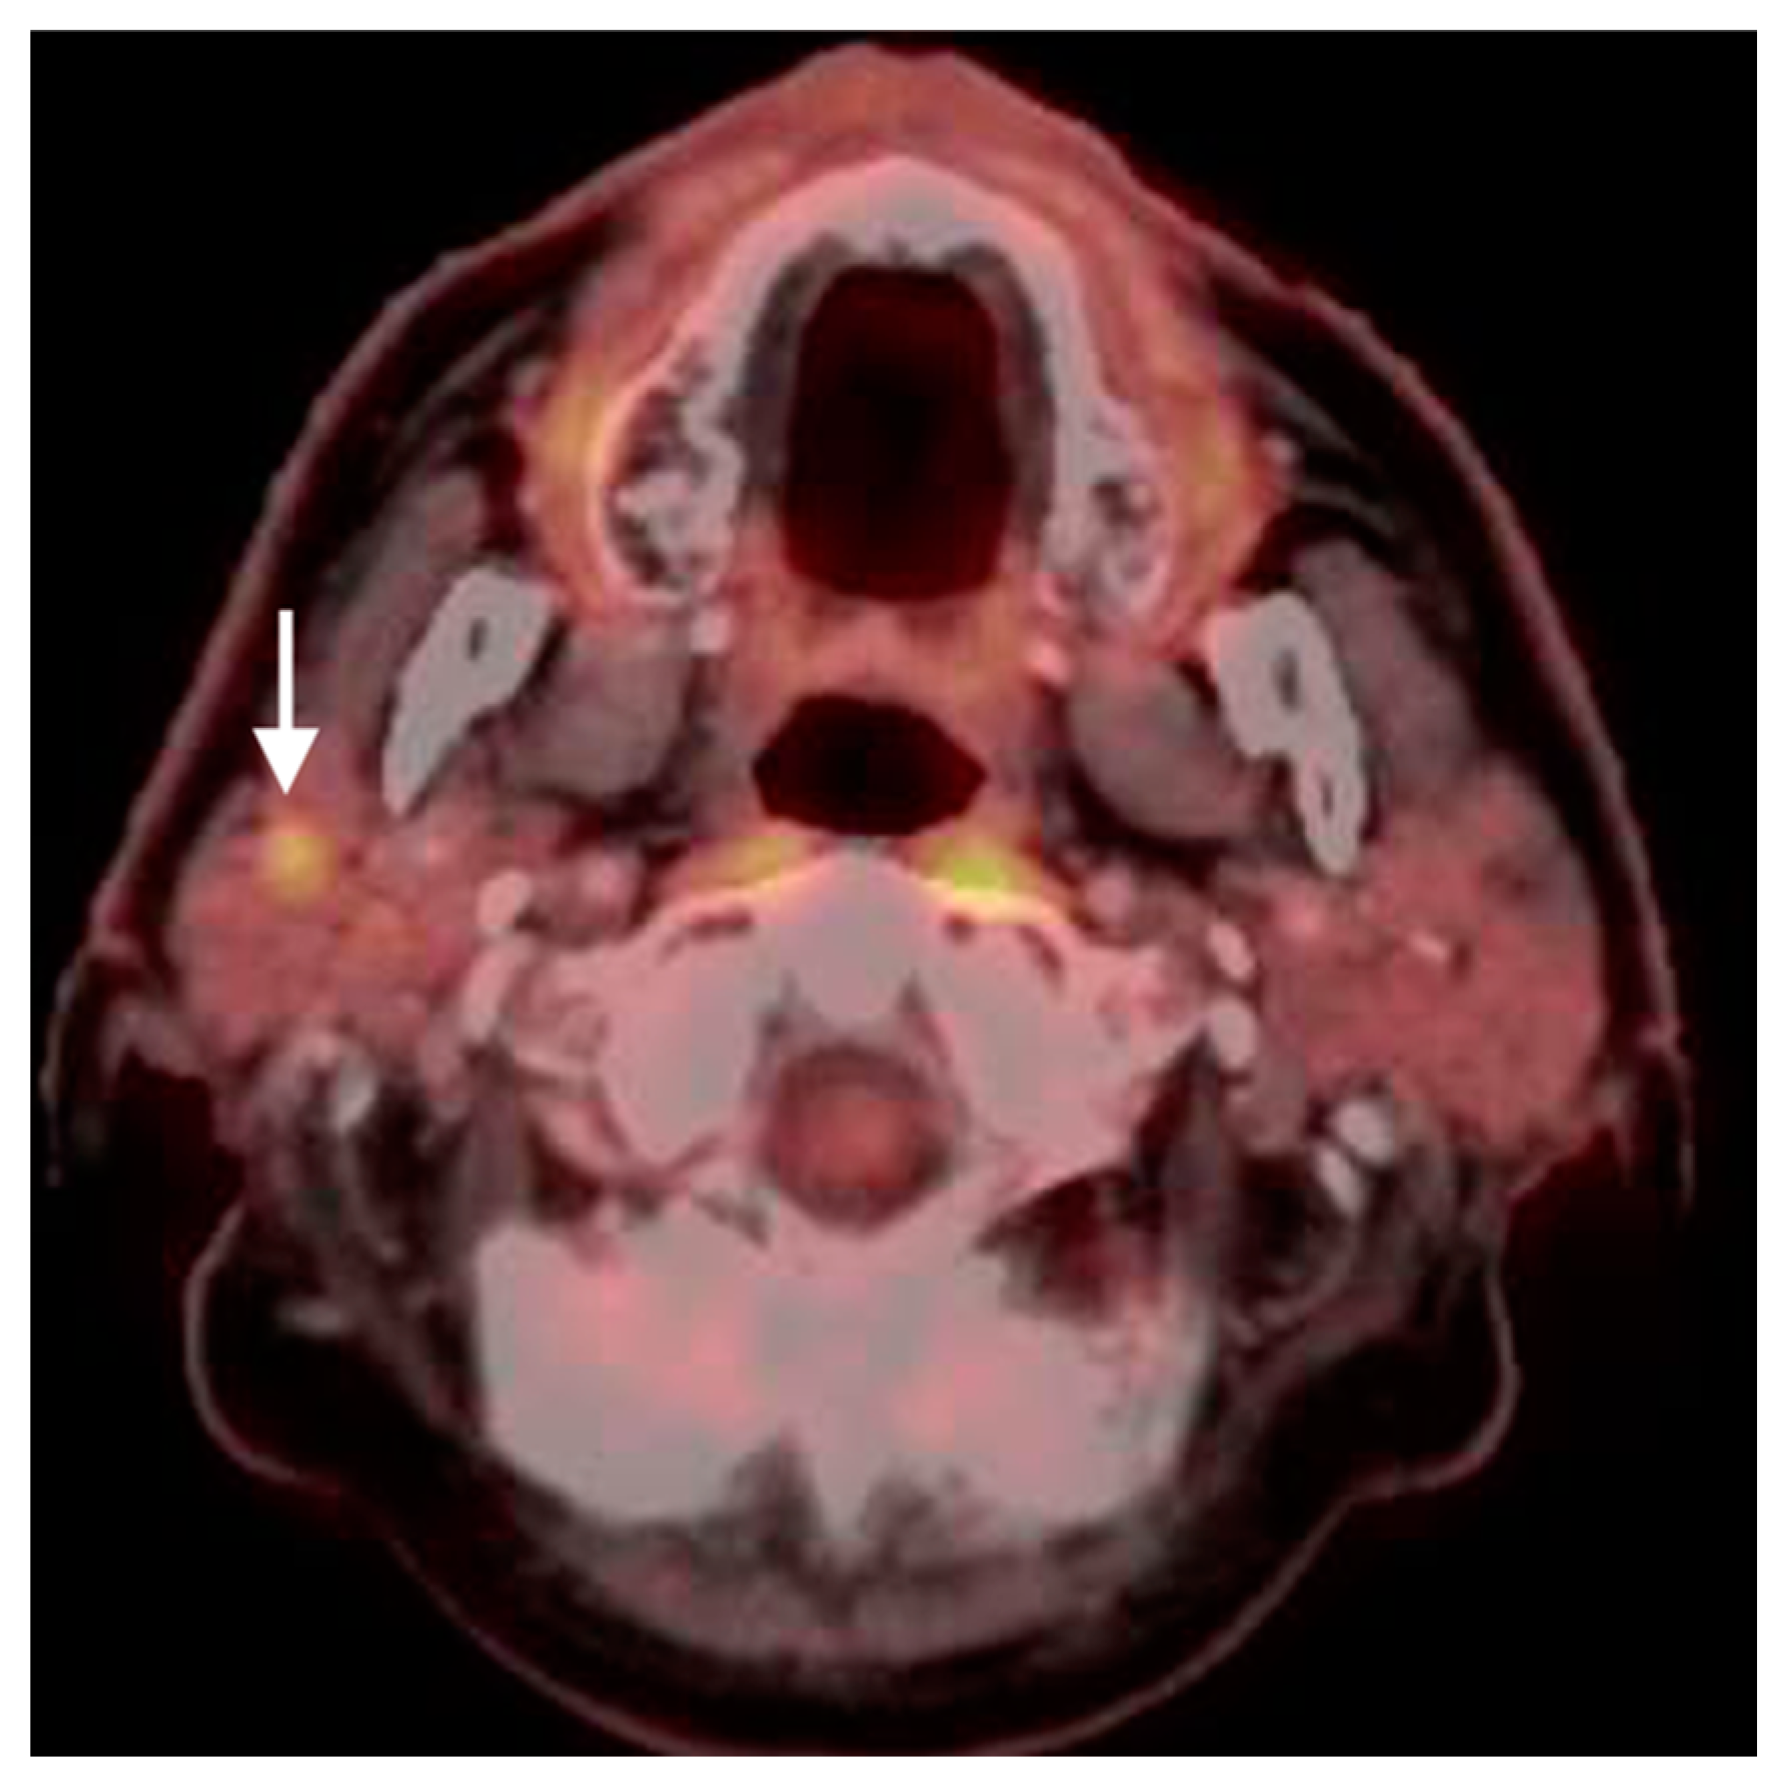

2.2. Squamous Cell Carcinoma of the Head and Neck (SCCHN)

2.3. Nasopharyngeal Carcinoma